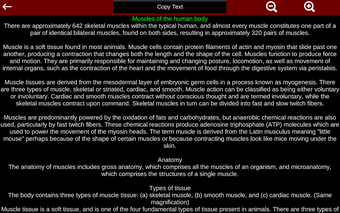

Esta herramienta educativa proporciona una descripción de cada músculo del cuerpo humano, así como un modelo tridimensional del sistema muscular. Con sólo tocar con el dedo, la aplicación revelará la información pertinente.